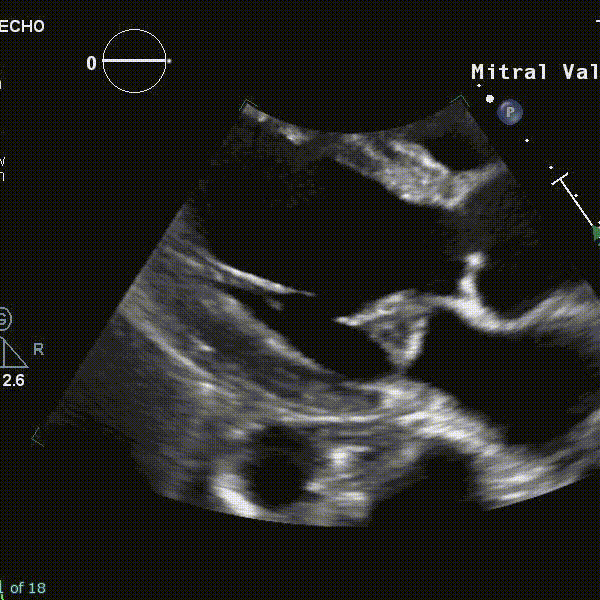

Malignant MVP

![[Mitral Valve Prolapse MVP-1745637451858.webp]] Figure source Transthoracic echocardiography demonstrating myxomatous bileaflet mitral valve prolapse (arrows) in cases 1 (A), 2 (B), and 3 (C). High-velocity mid-systolic spike (lateral annulus, 32 cm/s) in cases 1 (D), 2 (mid-systole, 19 cm/s) (E), and 3 (late systole, 25 cm/s) (F). (G) Normal medial annulus systolic velocity, case 1. (H) Tugging of the posteromedial papillary muscle by prolapsing leaflets (arrow), case 4. (I) Late-peaking systolic tissue velocity spike of 24 cm/s, case 4. (J) Pickelhaube, spiked German military helmet (reprinted with permission from the collection of Peter Suciu).